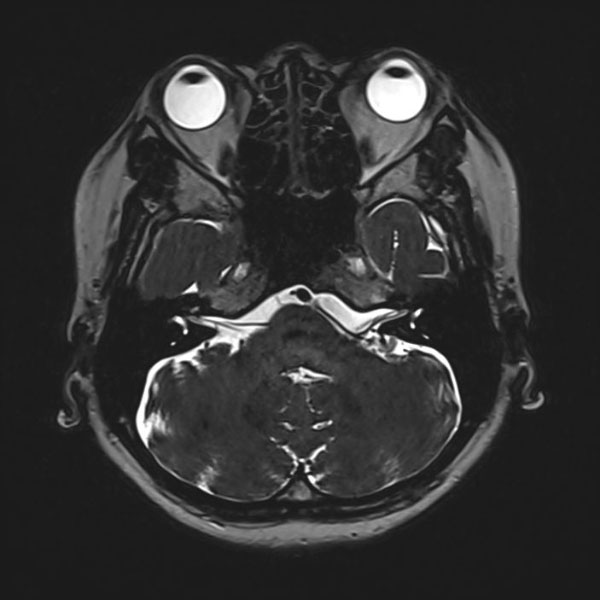

症例 '26年3月

No.

585

手術医師

手術年月

年齢

病名

術式

手術前

減圧前

減圧後

手術後

大阪府の病院

'26年3月

40代

左顔面痙攣

(痙攣をとること)

術後血管撮影